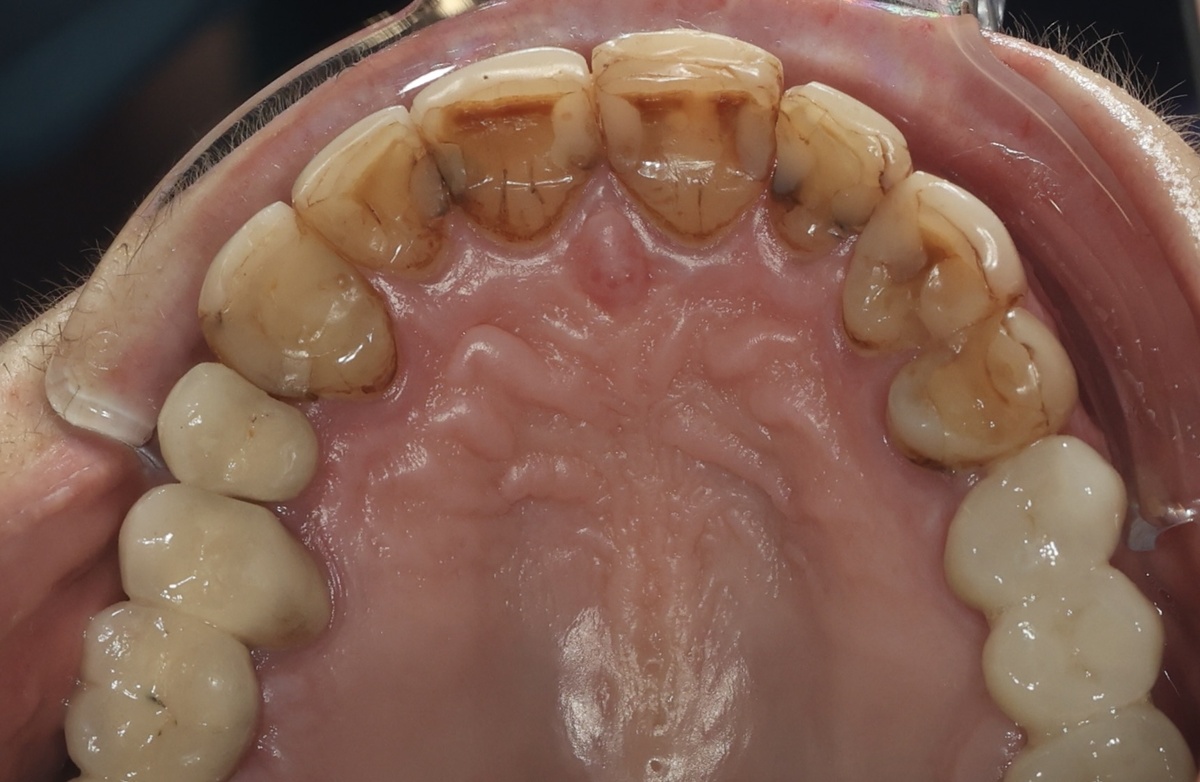

Дело хозяйское. Фото ещё до начала каких-либо работ:

Композитные виниры

Что касается эстетики, то тут советчиков быть не должно. Если человека устраивает внешний вид своих зубов, то нечего к нему лезть. Проходим мимо, дышим ровно.

Другое дело, если под композитом развивается что-то, что угрожает жизни зуба в перспективе - кариес, например. Он был обнаружен сразу, дело не хитрое: